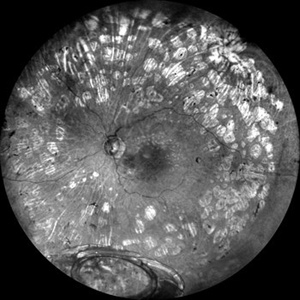

What Lies Beneath

Grey color fundus photograph of the left eye of a 78 year old gentleman who has undergone pars plana vitrectomy for proliferative diabetic retinopathy, shows dislocated intraocular lens bag complex lying on the inferior retina

Photographer: SHISHIR VERGHESE

Condition/keywords: dislocated intraocular lens (IOL), dislocated IOL, proliferative diabetic retinopathy (PDR)